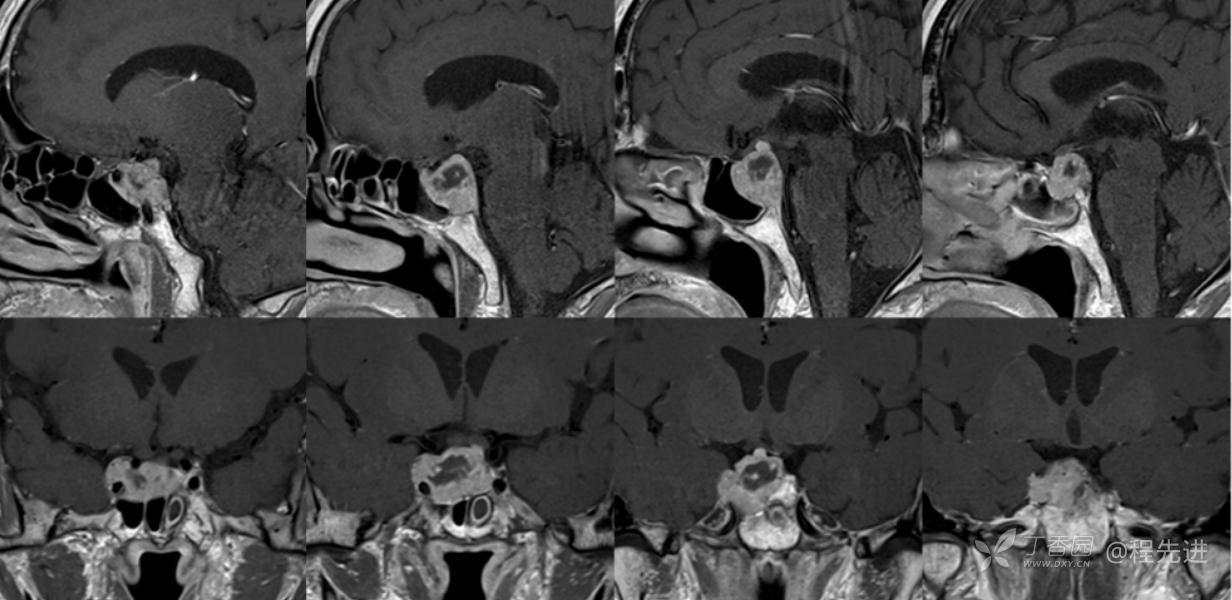

MR:

T1

T2

组合